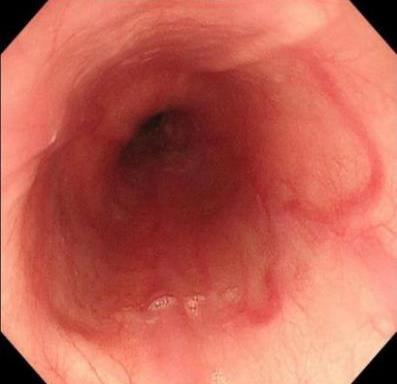

• 获得性免疫缺陷综合征合并马尔尼菲篮状菌导致肠道感染的内镜下表现(附6例报告)

2026, 32(3):84-88. DOI: 10.12235/E20250461

摘要 (32) HTML (27) PDF 3.50 M (26) 评论 (0) 收藏

摘要:目的 探讨获得性免疫缺陷综合征(AIDS)合并马尔尼菲篮状菌(TM)感染导致肠道感染的内镜下特征。方法 回顾性分析2022年11月-2024年10月于该院确诊为AIDS合并TM感染导致肠道感染的6例患者的临床资料。包括:临床症状、实验室检查、影像学检查、内镜检查和病理检查等。结果 6例患者中,男5例,女1例;发病年龄26~67岁;AIDS合并TM感染导致肠道感染患者的临床表现为:腹泻、腹痛、腹胀和恶心呕吐。其中,2例有消化道出血表现。实验室检查:6例患者外周血白细胞计数为(1.37~4.49)×109/L,血红蛋白计数为(67~99)g/L;CD4+T淋巴细胞为(1~52)个/μL,CD8+ T淋巴细胞为(61~321)个/μL,CD4+T淋巴细胞/CD8+T淋巴细胞比值为(0.01~0.18)。6例患者均行HIV RNA检测。其中,5例HIV RNA阳性。血培养:可见丝状真菌,报告显示为TM。影像学检查:6例患者CT结果可见肠系膜及腹膜后多发淋巴结肿大。内镜检查:6例患者内镜下均可见肠道病变。其中,十二指肠糜烂溃疡2例,结肠多发糜烂溃疡4例。病理检查:6例患者幽门螺杆菌(Hp)结果均为阴性,黏膜下可见成簇的小球形真菌孢子,符合TM感染;特殊染色:PAS(+),六胺银染色(+)。结论 当AIDS晚期患者出现消化道症状时,应警惕TM感染,病变部位常见于全结肠和直肠,亦可累及十二指肠,内镜下表现多为溃疡、糜烂和隆起性病变,形态表现无特异性;及时行胃肠镜检查、病理活检、特殊染色和免疫组化是确诊的关键。